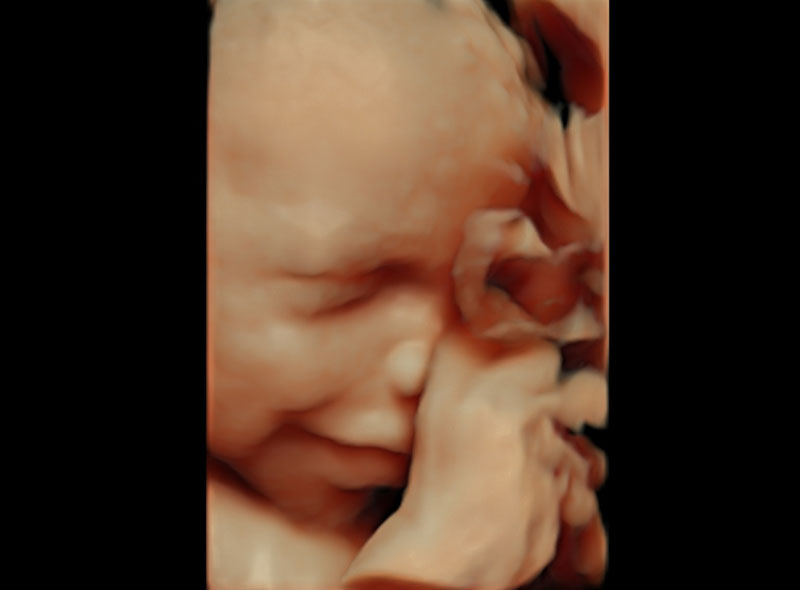

Anomaly scan remains one the cornerstone scans of pregnancy. It is known by different names like targeted scan, anatomy scan, malformation scan, second trimester scan, level 2 etc. All the above names reflect the primary purpose of the scan which is to assess the structure of the baby from head to toe and make sure that it is normal.

It is usually done at 19-20 weeks of pregnancy in every patient irrespective of prior scans. Doctors will study the baby’s structure in great detail and will be able to determine whether baby’s growth is on track. They will be able to pick up structural problems like heart defects, spine defects, brain defects etc. Not all findings highlighted in the scan, will need action. Many of these will only need a follow up and will be associated with normal outcomes. Some will need further testing - like amniocentesis to rule out genetic problems/infections etc. Unfortunately, some will be severe enough so that family is offered the option of termination of pregnancy. In our country this option is available till 24 weeks of pregnancy.